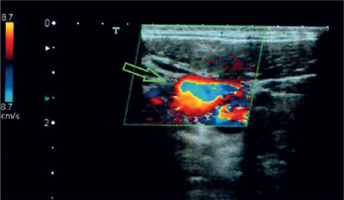

Figure 2

Color duplex ultrasound examination depicting the venous aneurysm with the “yin and yang sign” sign resulting from turbulent flow (arrow). This sign is usually seen in arterial aneurysms but may also be seen in venous aneurysms sporadically or during compression

Diagnosis of superficial VAs is primarily clinical [59, 64, 76]. Color duplex ultrasonography (CDU) is the first examination, as it is a non-invasive, inexpensive, and accurate technique [41, 45, 50, 58, 66, 87]. The VA appears as an anechoic cystic lesion in continuity with a superficial vein, which may contain hyperechoic intraluminal floating thrombus [4, 28, 46, 63]. It is easily compressible when probed and expands after pressure is released [46, 63]. CDU differentiates between arterial and VAs and depicts the feeding vessels [41, 48, 50, 57, 61]. The so-called “yin and yang sign” seen in arterial aneurysms, due to turbulent flow, may appear spontaneously or during compression in VAs [12, 46]. However, CDU may fail to diagnose a superficial VA when the feeding vessels are too small, the aneurysm is thrombosed, or in cases of complex anatomy and special patient habitus [52, 68].